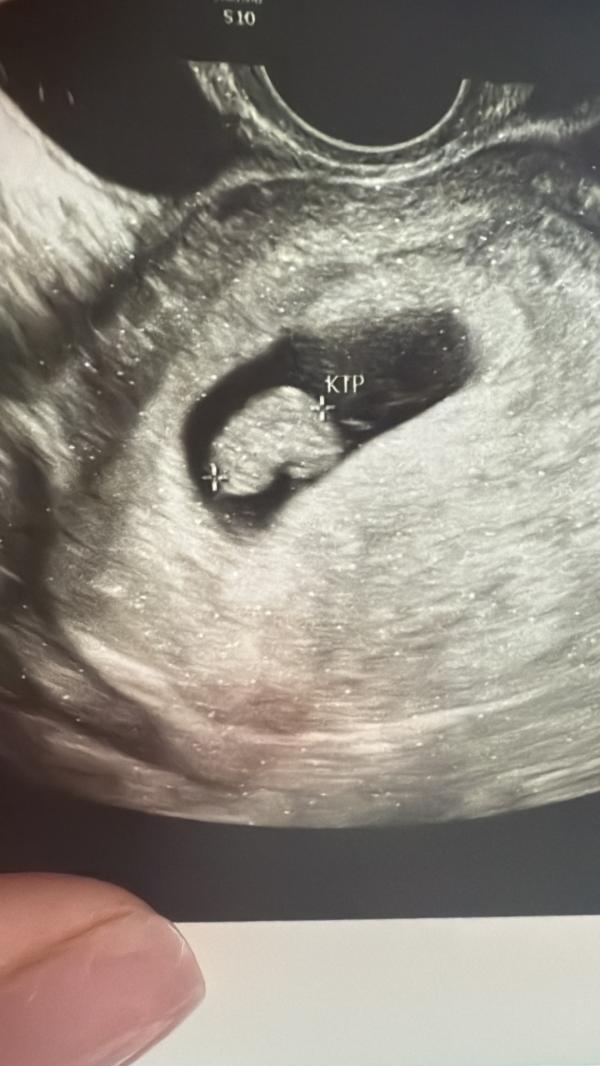

Сначала узистка сказала что все ок, идем на 7,2 по сроку,чсс поставила 120, хотя вчера по животу поставили 160 и меня это смутило. Явно кто-то где-то не так насчитал,а может разности аппаратов. И снова бесконечная неделя ожидания. По ктр малыш подрос.